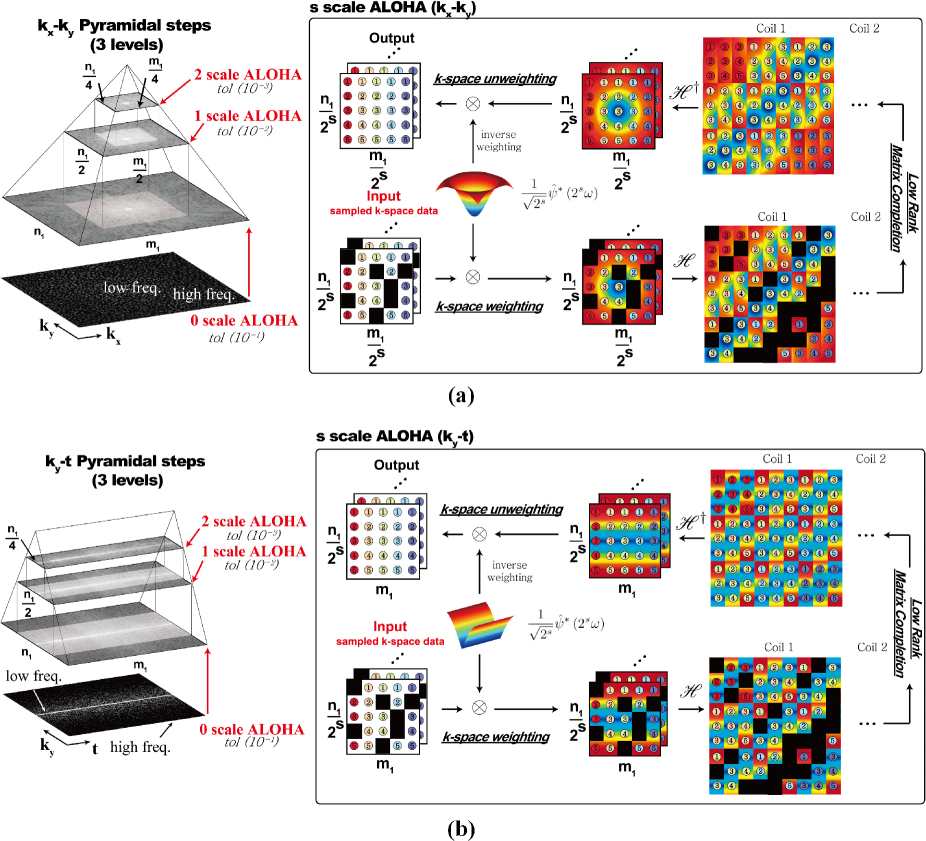

where and the superscript ∗ denotes the complex conjugate. Note that sampling interval for widens by factor of 2 for each successive scale to construct the k-space weighting vector . Consequently, we have a pyramidal decomposition as shown in Fig. 1, and the ALOHA (III-A) should be solved from the lowest scale, i.e. , up to the highest scale (see caption of Fig. 1 for more discussion of the figures). Because sparsity can be imposed only on the wavelet coefficients, the low frequency k-space data that correspond to the scaling function coefficients should be acquired additionally during MR data acquisition. This information as well as the annihilating filter size then determines the the depth of the pyramidal decomposition as will be discussed in detail later.

As shown in Fig. 1, the ALOHA framework is comprised with several major steps: pyramidal decomposition, k-space weighting, Hankel matrix formation, rank estimation, SVD-free low rank matrix completion, and k-space unweighting. Here, we will explain these in more detail.

The pyramidal decomposition is performed as follows. First, in static MR data acquisition illustrated in Fig. 1(a), the corresponds to the two phase encoding directions that are downsampled. Thus, the Hankel matrix is constructed from data. After a k-space interpolation from a finer scale, the data at the current scale is defined to contain one-fourth of data around zero frequency from that of the previous scale. Second, in the case of dynamic MR imaging shown in Fig. 1(b), samples from the readout direction are fully acquired, whereas the directional phase encoding are downsampled along the temporal direction . Therefore, the data in space (or simply, space) are downsampled, from which we construct a Hankel structure matrix. In pyramidal decomposition, after a k-space interpolation from a finer scale, the data in the current scale contains a half of the data from that of the previous scale. Note that the wavelet decomposition is performed only along the spatial domain, so the pyramidal decomposition is only performed along direction. This construction of Hankel matrix is due to the observation that the dynamic signal is sparse in spatial wavelet and temporal Fourier transform domain [42]. See more details in our recent work [42].

The k-space weighting is performed using wavelets. Specifically, based on our discussions on maximally localized smoothing function, we use a Haar wavelet expansion whose spectrum is given by

For the case of static MRI in Fig. 1(a), we use 2-D weighting by assuming that the image is sparse in 2-D dyadic wavelet transform domain. Care needs to be taken when applying the weighting to 2D Fourier domain because there are two frequency variables . One could use a separable weighting ; however, the resulting problem is that the missing k-space components along the frequency axis or cannot be recovered. Consequently, we applied the weighting sequentially along each axis, i.e. we solve (II) by applying first, which is followed by solving (II) with . However, simultaneous weighting would be possible as demonstrated in a recent work for off-the-grid recovery of piecewise constant image [43]. For the case of dynamic imaging in Fig. 1(b), one dimensional weighting along the phase encoding direction was applied as explained in detail in [42]. Finally, after the k-space interpolation, the k-space unweighting is done in k-space pixel-by-pixel by dividing the reconstructed value with (98). Note that (98) has zero value at the DC frequency. However, because we acquire the DC value as well as some of the low frequency k-space data, the problem of dividing by zero never happened.